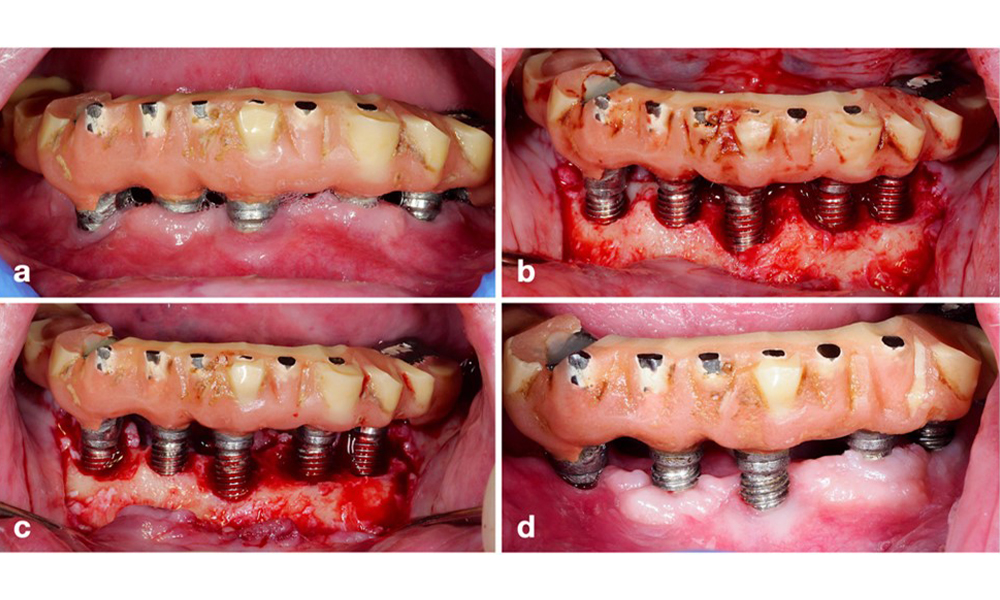

Une approche résective (c'est-à-dire une gingivectomie et/ou un lambeau positionné apicalement, avec ou sans remodelage osseux) doit être choisie dans les cas de perte osseuse principalement horizontale ou de défauts larges, où le potentiel de régénération osseuse est limité (figure 11).

Pour les implants dont la surface est modifiée et dans les régions où la régénération osseuse est improbable, l'implantoplastie doit être envisagée. Cette procédure consiste à retirer les fils de l'implant et à lisser la surface micro-structurée de l'implant à l'aide d'instruments rotatifs (figure 12). Cette approche facilite la décontamination complète de la surface de l'implant et, surtout, améliore le contrôle du biofilm postopératoire (Bertl et Stavropoulus 2021 ; El Chaar et al. 2020 ; Geremias et al. 2017). Faute de preuves cliniques suffisantes, le rôle de l'implantoplastie est controversé (Herrera et al. 2023 ; Ramanauskaite et al. 2021), mais les craintes concernant l'induction d'une inflammation par le dépôt inévitable de particules de titane et le risque accru de fracture de l'implant en raison de la réduction de sa résistance n'ont pas été étayées (Stavropoulos et al. 2019).